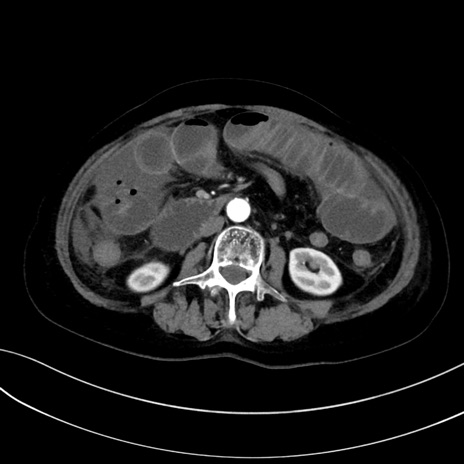

症例13 CT(横断像)1日半後